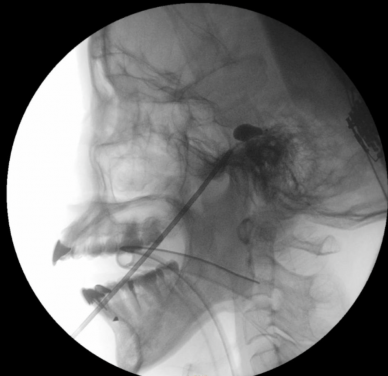

PBC is an interventional technique designed to alleviate pain associated with the trigeminal nerve, which is responsible for facial sensation. The procedure involves inserting a tiny balloon through the cheek into the trigeminal ganglion near the base of the skull and inflating it with contrast medium to gently compress the nerve’s pain fibres. Proper placement is confirmed by fluoroscopic imaging, which shows the characteristic pear-shaped appearance of the balloon.